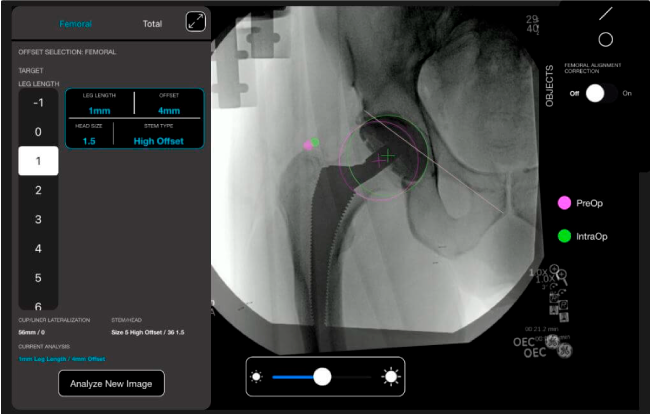

Datos procesables en tiempo real para la toma de decisiones.

Favorece la restauración biomecánica del offset femoral.

Desplazamiento y offset para posicionamiento óptimo del componente (vástago) femoral.

Con tecnología ONETRIAL® que calcula automáticamente el cambio en la longitud de la pierna y el desplazamiento para todas las combinaciones de implantes en una tabla fácil de leer.